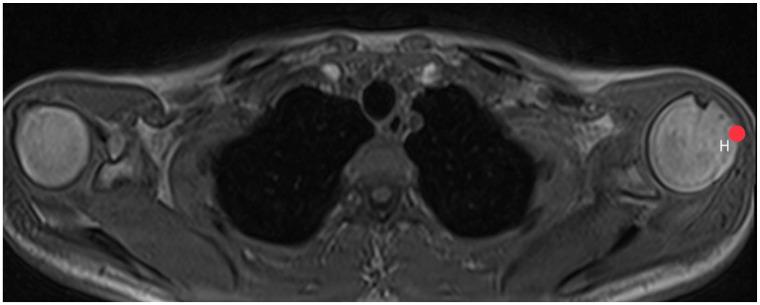

Shoulder pain is a common issue often linked to conditions such as subacromial impingement or rotator cuff lesions. The role of the acromion in these symptoms remains a subject of debate. This study aims to establish standardized values for commonly used acromion dimensions based on whole-body MRI scans of a large and healthy population and to investigate potential correlations between acromion shape and influencing factors such as sex, age, BMI, dominant hand, and shoulder pain. The study used whole-body MRI scans from the Study of Health in Pomerania, a German population-based study. Acromion index, acromion tilt, and acromion slope were measured. Interrater variability was tested with two independent, trained viewers on 100 MRI sequences before actual measurements started. Descriptive statistics and logistic regression were used to evaluate the results. We could define reference values based on a shoulder-healthy population for each acromion parameter within the 2.5 to 97.5 percentile. No significant differences were found in acromion slope, tilt, and index between male and female participants. No significant correlations were observed between acromion morphology and anthropometric parameters such as height, weight, or BMI. No significant differences were observed in acromion parameters between dominant and non-dominant hands or stated pain intensity. This study provides valuable reference values for acromion-related parameters, offering insight into the anatomy of a healthy shoulder. The findings indicate no significant differences in acromion morphology based on sex, weight, BMI, or dominant hand. Further research is necessary to ascertain the clinical implications of these reference values. The establishment of standardized reference values opens new possibilities for enhancing clinical decision making regarding surgical interventions, such as acromioplasty.

肩部疼痛是一个常见问题,通常与肩峰下撞击或肩袖损伤等病症有关。肩峰在这些症状中所起的作用仍是一个有争议的话题。本研究旨在基于对大量健康人群的全身MRI扫描,建立常用肩峰尺寸的标准化值,并研究肩峰形状与性别、年龄、体重指数、优势手和肩部疼痛等影响因素之间的潜在相关性。该研究使用了来自德国基于人群的波美拉尼亚健康研究的全身MRI扫描数据。测量了肩峰指数、肩峰倾斜度和肩峰斜率。在实际测量开始前,由两名独立的、经过培训的观察者对100个MRI序列进行了观察者间变异性测试。使用描述性统计和逻辑回归来评估结果。我们可以根据肩部健康人群为每个肩峰参数在第2.5至97.5百分位数内定义参考值。在男性和女性参与者之间,肩峰斜率、倾斜度和指数没有发现显著差异。在肩峰形态与身高、体重或体重指数等人体测量参数之间未观察到显著相关性。在优势手和非优势手之间或所述疼痛强度方面,肩峰参数没有观察到显著差异。本研究为与肩峰相关的参数提供了有价值的参考值,有助于深入了解健康肩部的解剖结构。研究结果表明,基于性别、体重、体重指数或优势手,肩峰形态没有显著差异。有必要进行进一步研究以确定这些参考值的临床意义。标准化参考值的建立为加强关于手术干预(如肩峰成形术)的临床决策开辟了新的可能性。